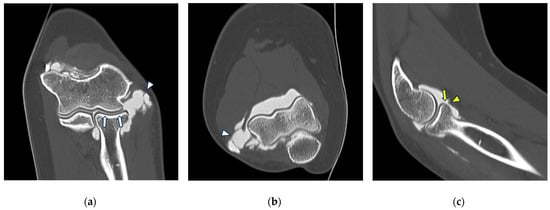

Figure 2.

CT arthrography of the elbow—normal anatomy. (a) Coronal image shows a regular chondral lining of the radio-humeral, ulno-humeral, and radio-ulnar joints, with no evidence of focal chondral lesions. The articular capsule is not pathologically distended and there is only a physiological amount of contrast in the lateral radio-humeral recess (asterisk), indicating the presence of an intact radial collateral ligament; (b) sagittal image shows an undisplaced annular ligament (white arrowhead), as well as a regular chondral lining of the radial head side and a physiological sliver of contrast in the annular recess (white arrow); (c) axial image shows a physiological amount of fluid in the posterior recess of the elbow (yellow arrow), with no evidence of loose bodies, as well as regular chondral lining of the humerus and olecranon.